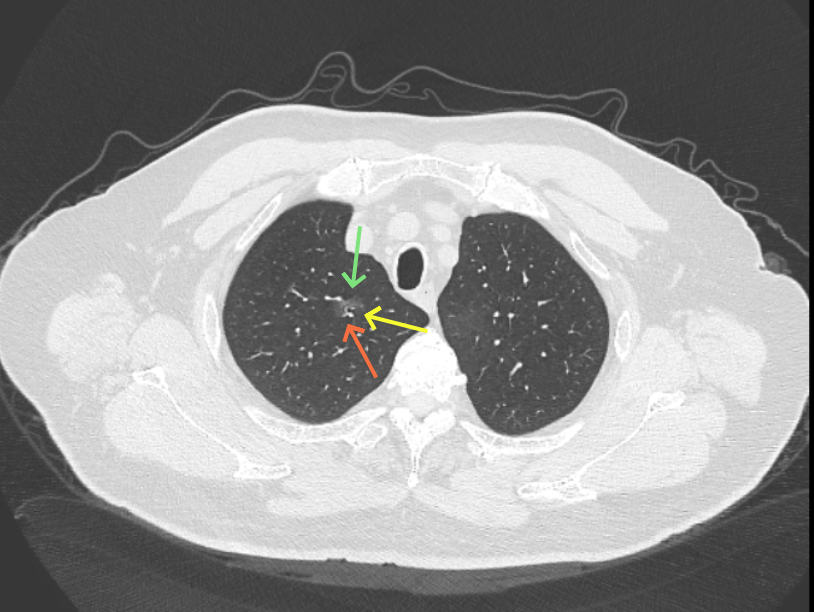

但病灶B却显然进展!变成以实性成分为主的了!

两处均有进展,混合密度这处更显著些。那要考虑手术了的。之前也有碰到较短时间内进展是伴炎症或纤维增生的,但我们不能赌。建议手术为宜。意见供参考!

再看病灶B的2026年3月细节影像特征:

上图是混合密度,轮廓较清,瘤肺边界欠清晰。

病灶A以及他处磨玻璃结节其实进展都是不明显的,略与2022年比,病灶A稍显明显点。病灶B开始时极淡,之前进展虽有但也甚微,直到2025年9月仍是磨玻璃成分为主,只是点状少许密度稍高成分。但在最近半年内却显然进展!若从影像上判断,基本上就得是浸润性腺癌了。那有几点:一是必不能再随访;二是大小来看仍是1A期;三是从快速进展来说,可能含有部分高危亚型,比如微乳头或实体型等;四是他处的磨玻璃结节以及病灶A显然不能用病灶B的转移来解释,仍考虑是多原发早期肺癌。

结友问能否先穿刺?我是这么考虑的:你这个病灶B一是位置深,且靠近附近的血管,不容易穿刺;二是从影像变化来看,基本上肯定是恶性的,不是100%,也是95%以上的概率。刚才我又在重建看冠状位与矢状位以及各次影像,目前混合密度的其实是后来者居上,原来刚开始是它比旁边的病灶密度淡的,但它的密度不是太纯,前次你自己也说似乎有点状偏实性成分。只是最近这半年进展特别快。这说明它的恶性程度较它边上原来就比较明显的那处恶性程度高,亚型中大概率有低分化的成分。所以从目前的影像来看,要尽快手术,而且切肺叶更为稳妥些。

这是较为少见的一个病例,磨玻璃为主,而且一直瘤肺边界欠清晰的病灶何以会在之前三年均极缓慢微小变化的情况下,近半年却快速进展呢?从影像细节上看,我们能否进一步分析哪种纯磨玻璃结节可能会较快进展?结合本例,我个人的考虑是:1、病灶整体显得是磨玻璃密度,但灶内并不均匀,就如磨玻璃密度中混入细沙状;2、整体轮廓虽然较清但瘤肺边界相对来说却并不太清晰;3、邻近有血管紧挨,而且与病灶这间缺乏间隙;4、病灶密度不高,没有明显实性成分,却有灶内有细支气管通气征,说明肿瘤成分具有收缩力,却与纯磨的收缩不匹配(纯磨一般不太会有明显收缩力)。如果有上面这些特征可能要提高警惕,一是适当较短的随访间隔,二是影像细节变化要更加注意,开始变化意味着已经进入发展期,而非蛰伏期。当然是否在2025年9月时定得手术了?如果是孤立性的病灶B,且位置位于能简单楔形切除的位置,那是可以考虑的。但位置深、两肺多发,切除范围不小,再今年据肺癌诊疗指南中说的混合磨玻璃结节实性成分不足25%是非侵袭性病变,且几乎不会转移,那么按原则仍再随访显然是可以的。本例的随访变化再次表明磨玻璃密度肺癌的诊疗个体化之路仍是很漫长的,按指南原则的随访或诊疗显然不足以覆盖所有病例,总结与经验积累永远在路上。